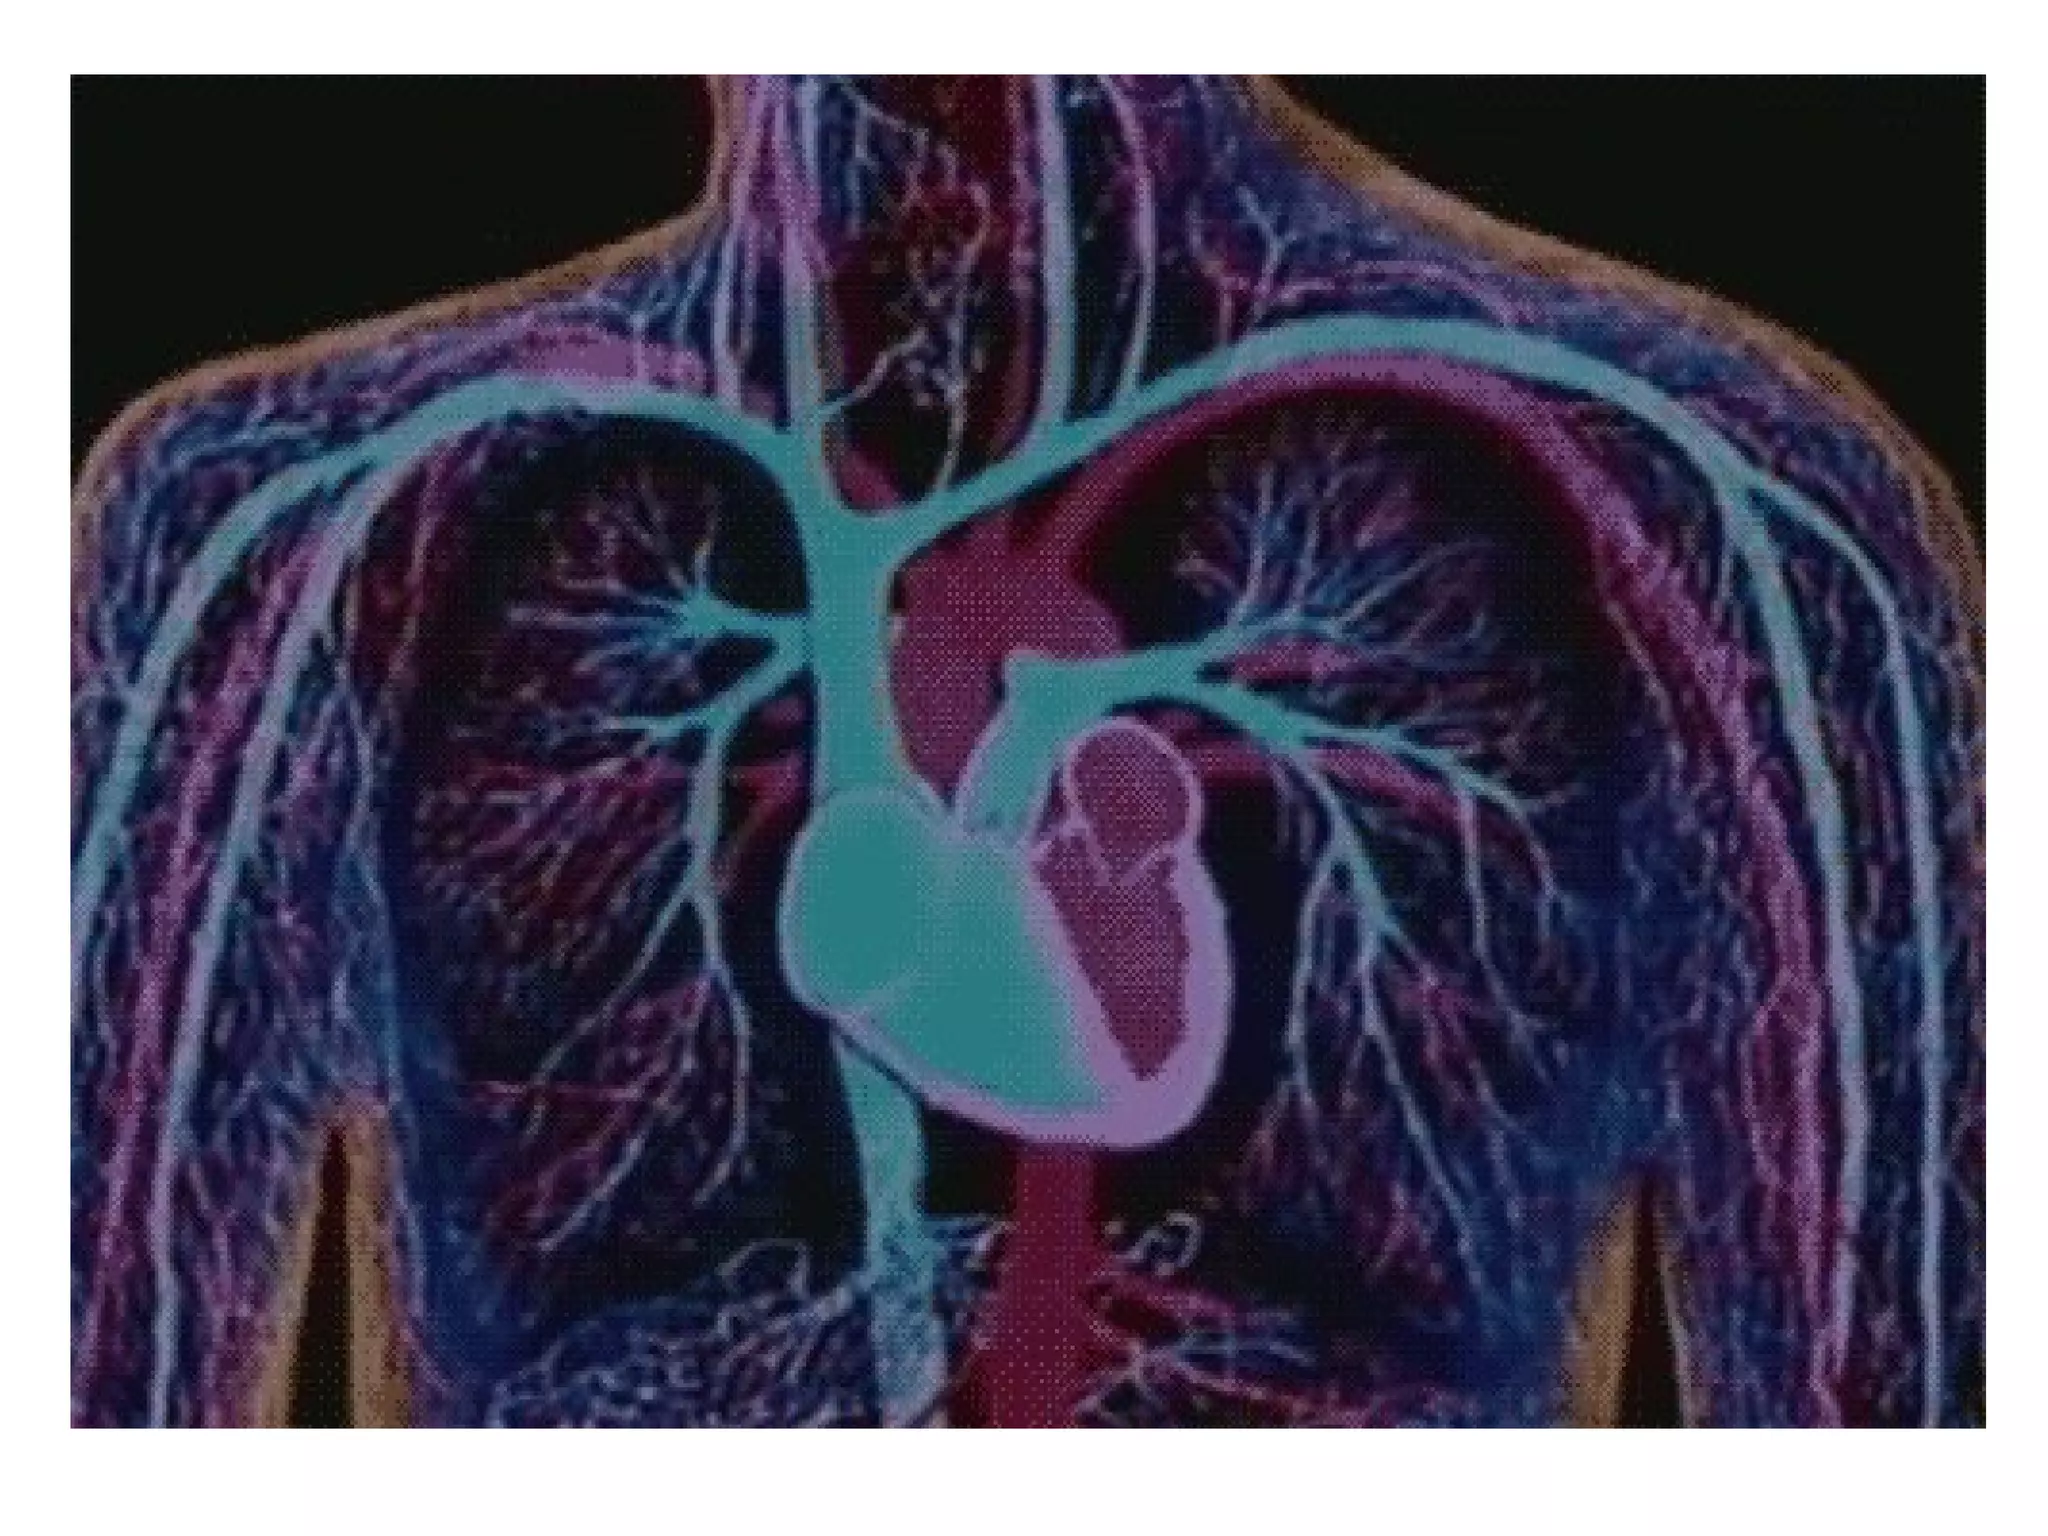

• KARDIOVASKULARNI SISTEM čineKARDIOVASKULARNI SISTEM čine

: SRCE , cirkulacijski sistem: SRCE , cirkulacijski sistem

(arterije , vene i limfatici) .(arterije , vene i limfatici) .

• SISTEMSKU cirkulacijuSISTEMSKU cirkulaciju čine levačine leva

komora , arterije , arteriole ,komora , arterije , arteriole ,

kapilaru, venule , vene , gornja ikapilaru, venule , vene , gornja i

donja šuplja vena i desnadonja šuplja vena i desna

pretkomora )pretkomora )

• Plućnu cirkulacijuPlućnu cirkulaciju čine desnačine desna

komora, plućna arterija, kapilari,komora, plućna arterija, kapilari,

plućne vene i leva pretkomora .plućne vene i leva pretkomora .